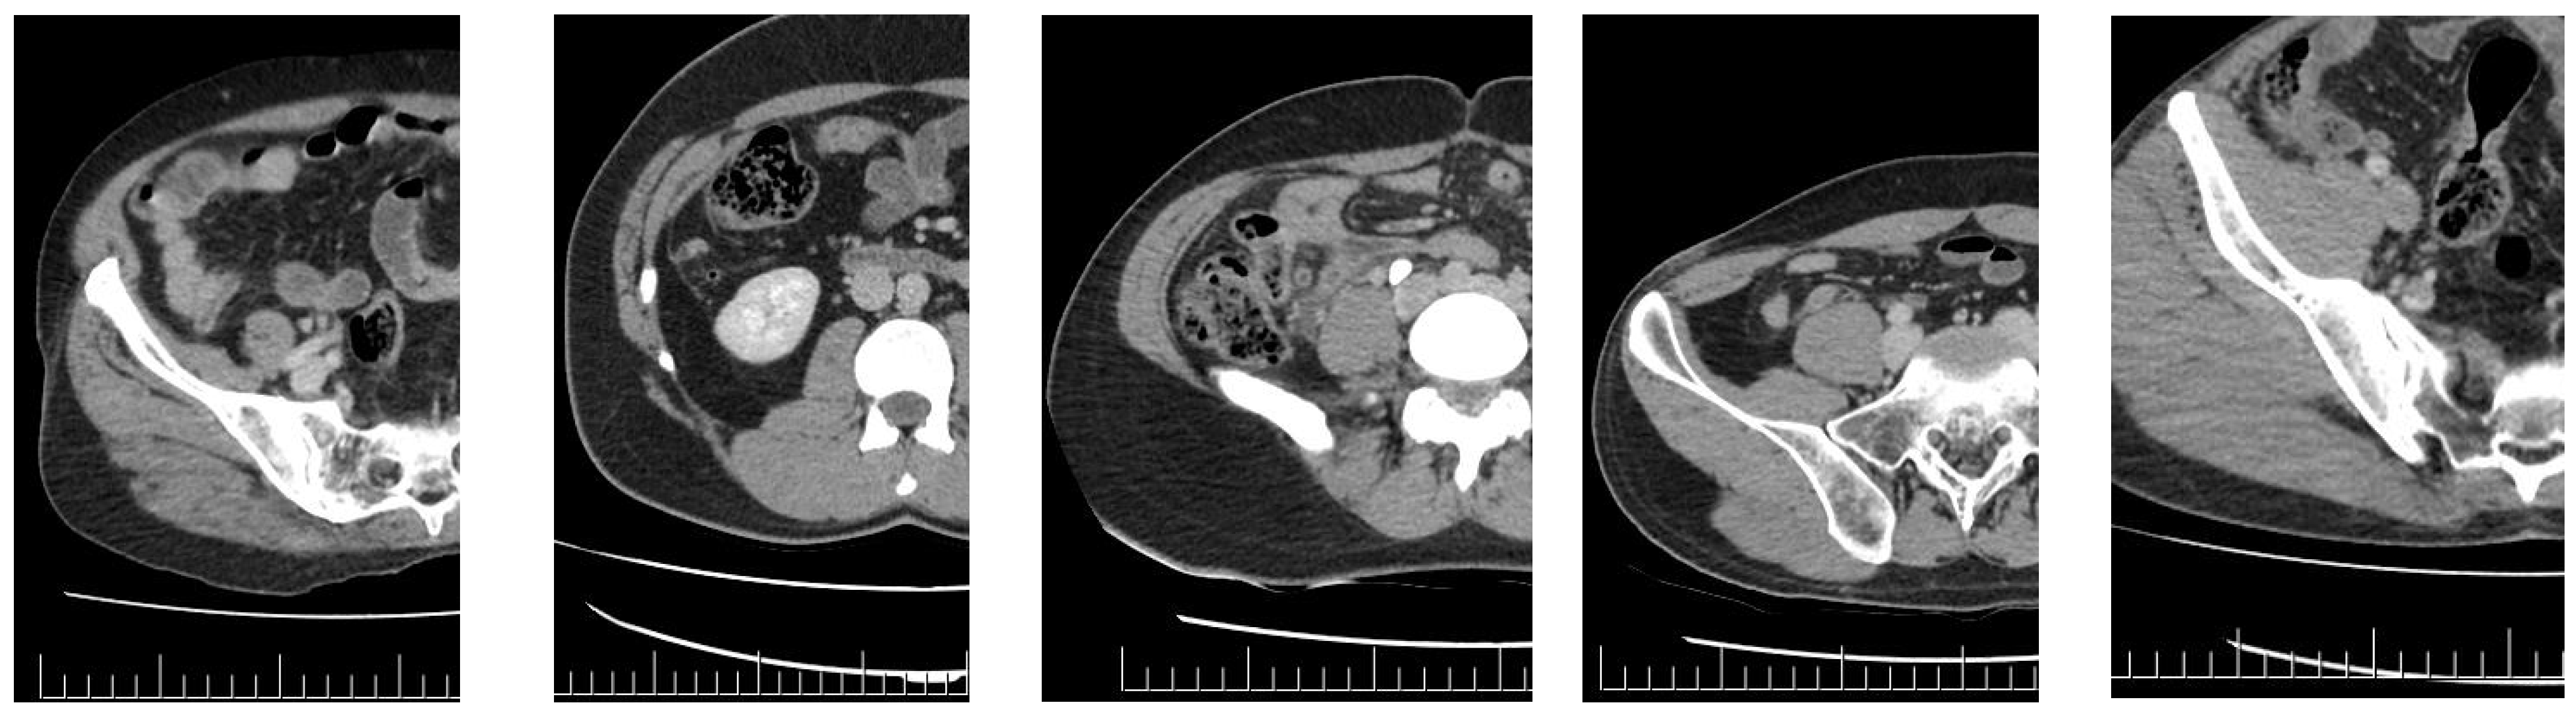

Group 1 included 66 patients, whereas Group 2 included 200 patients. The study criteria for Groups 1 and 2 are illustrated in Figure 1 and Figure 2, respectively.

4.2.1. Group 1

Group 1 included cases with borderline and moderate appendiceal double-wall thickness, ambiguous peri-appendiceal edema indicating inflammation, and no appendicoliths. No radiologist reported a conclusive diagnosis of AA based on the patient’s CT image. Notably, some reports omitted the appendix, some stated that it was normal, and others had ambiguous references, such as possible signs of appendicitis, and advised further examinations. Group 1 included cases in which the radiologists were uncertain about the presence of AA, highlighting the importance of this study. Multiple radiologist remarks, such as a normal appendix and suspicion of AA, were grouped for analysis. Subsequent research should consider analyzing these reports individually.

Appendiceal Diameter

The appendiceal diameter was assessed in this study as follows: in the control group, the maximum appendiceal double-wall thickness was 10 mm. The threshold was set to 9 mm because only a few participants in the control group had a diameter of 10 mm. Briefly, the appendiceal diameter did not serve as a distinguishing parameter in this group because the double-wall thickness ranged from 6 mm to 9 mm in both the patient and control groups. Appendiceal diameter is a straightforward sonographic criterion that exhibits good agreement among radiologists in cases of suspected AA [25]. Notably, some studies have found that the appendiceal diameter is not influenced by age and can exceed 6 mm in 42% of asymptomatic patients, hindering its effectiveness in diagnosing AA. Some studies also indicate that 23% of adult men have appendages that are healthy in terms of the cecum and larger than 6 mm in diameter. Therefore, they suggest that when an appendix is found with a diameter between 6 and 9 mm, it should be considered “undetermined” and other findings of AA should be investigated [26]. Conversely, it has been reported that the appendiceal diameter does not play a major role in ruling out complex appendicitis [27]. The results for appendiceal diameter in this study are consistent with those of previous studies. Furthermore, a comparable increase in the appendiceal diameter may be observed in cases of ovarian cyst rupture and inflammatory bowel disease. In this study, we deliberately excluded patients with different primary conditions in the right lower quadrant. We identified patients with AA based on comparison with a healthy control group. Future research on this quadrant should aim at distinguishing between AA and other disorders.

Pericecal Fat Tissue

Pericecal fat tissue acts as an inherent contrast agent, making peri-appendiceal inflammation the most notable finding on non-contrast CT, with a sensitivity of 98–100%. This criterion was prioritized in our classification because of this significance. Edema in this region was assessed as a basis for classification into Group 1, and the subjectivity involved with assessing peri-appendiceal inflammation was addressed through the establishment of three quantifiable criteria: (1) having thinner edema compared to the thickness of the single appendiceal wall or the opposing wall; (2) restricted distribution of edema throughout the wall; and (3) edema not entirely encircling the wall. If at least one of these criteria was met, the edema was classified as mild, and the patient was placed in Group 1. These criteria were helpful in providing some level of objectivity; however, they were still based on personal opinions. For example, widespread occurrence is indicated in the second requirement. These criteria could be more explicitly articulated.

The success rate of deep learning for Group 1 diagnosis was 83.3%, which is relatively high. However, this approach did not result in diagnosis for a substantial proportion of cases. Fewer patients were included in this group than in the other groups. Increasing the number of cases and studies using various methodologies could enhance the diagnosis rate.

Figure 1. Study criteria for Group 1 (<9 mm diameter and absence of obvious edema).